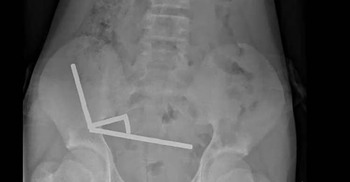

নিউজিল্যান্ডে ১৩ বছর বয়সী এক কিশোর বেশ কয়েকটি শক্তিশালী চুম্বক গিলে ফেলায় মারাত্মকভাবে অসুস্থ হয়ে পড়ে। শেষ পর্যন্ত অস্ত্রোপচারের মাধ্যমে তার অন্ত্রের একটি অংশ কেটে ফেলতে হয়। ঘটনাটি সম্প্রতি নিউজিল্যান্ড মেডিকেল জার্নাল-এ প্রকাশিত এক কেস রিপোর্টে উল্লেখ করা হয়েছে...